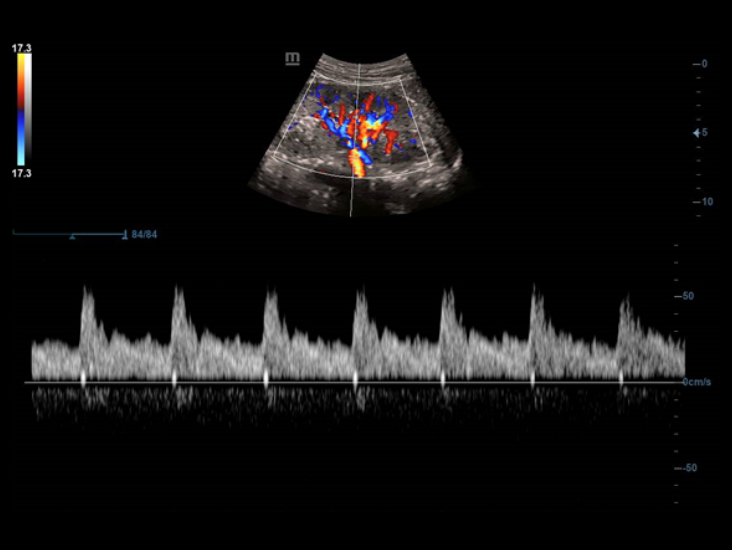

Smart Track

Smart Track menyediakan optimasi yang cepat dan cerdas untuk pencitraan vaskular dengan operasi satu sentuhan yang sederhana. Alat ini bisa mengoptimalkan spektrum Warna, Daya, dan PW dengan melakukan pelacakan mandiri dan mengurangi langkah-langkah yang menghabiskan waktu. Oleh karena itu, alur kerja pemeriksaan vaskular disederhanakan dengan tampilan yang optimal.